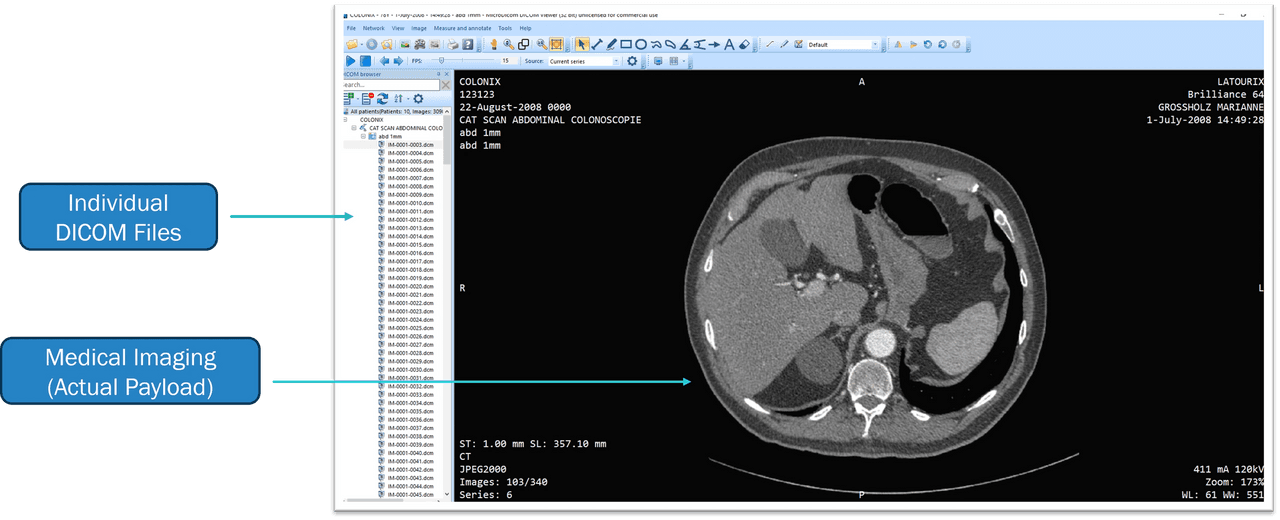

The DICOM File: A Container of Wonders

The DICOM Header: Your Guide to the Contents

Much like the detailed labels on a shipping container, a DICOM file’s payload is carefully enclosed within a digital 'container.' On the exterior, a DICOM header serves a similar function to a container's handling instructions and labels. This header conveys crucial data, guaranteeing that the image's meaning, context, encoding, and additional critical details are recorded with precision. The header does more than simply present the image; it narrates the journey from its creation to its final destination, weaving in the patient's story and ensuring the image is more than a picture — it's a chapter in a medical narrative.

Inside the DICOM File: Unveiling the Payload

Now, let's peek inside. Beyond the header lies the actual DICOM payload. It's not just an image; it's a constellation of pixels, each carrying a fragment of a larger story about a patient's health. This is what the medical professionals are after - the 'goods' that the DICOM standard safeguards and delivers.